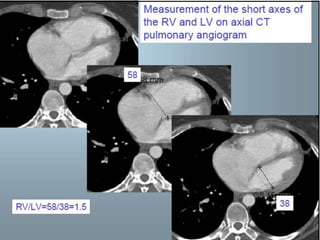

 RV dilation

 RV/LV short axis >1= pulmonary

hypertension

 RV/LV short axis >1.5= severe PE

 Leftward septal bowing

 RV dilation RV/LV short axis >1= pulmonary hypertension  RV/LV short axis >1.5= severe PE  Leftward septal bowing